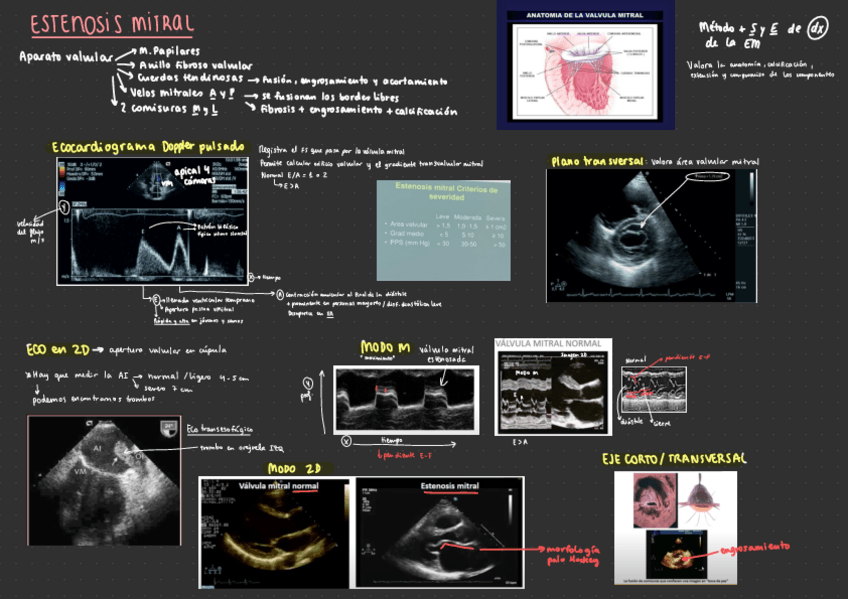

Tema-2.-Valvulopatias-izquierdas.pdf